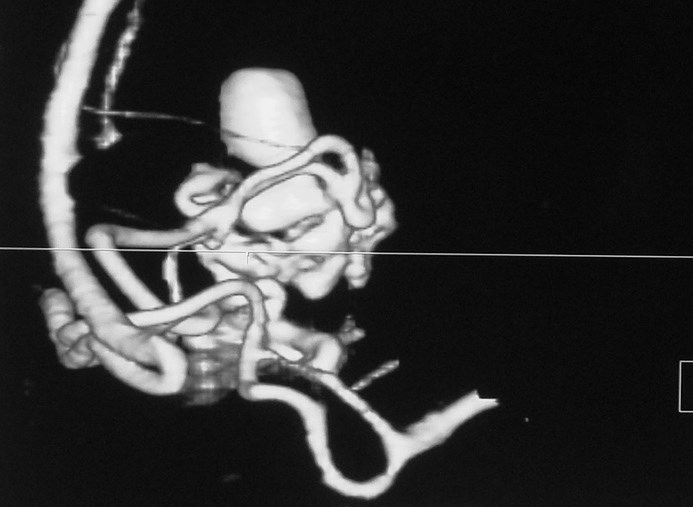

Arteriovenous malformations

Arteriovenous malformations of the brain are abnormal bunch of blood vessels that can rupture causing bleeding, or may cause seizures. Brain imaging (CT, MRI) is required for early diagnosis, while definitive treatment is carried out after cerebral angiography. Treatment implies craniotomy and excision of the AVM, which can be done safely in majority of the cases. Embolisation and radiosurgery are acceptable substitutes, but carry risk of further bleeding.